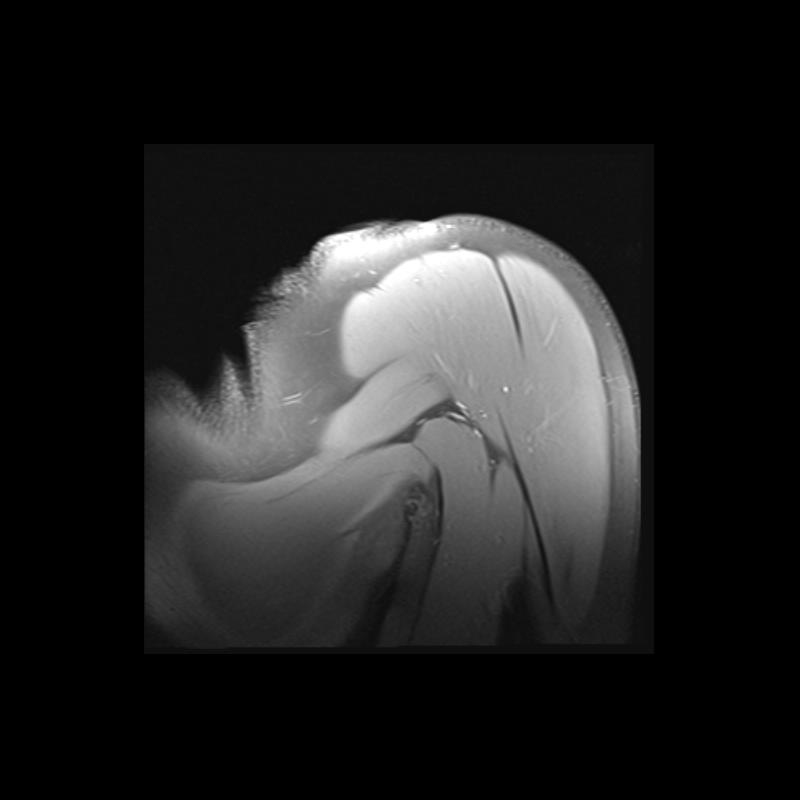

Shoulder MRI Anatomy